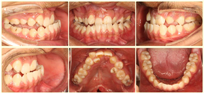

口外检查(图1):

正面观:下颌及颏部右偏3mm,双侧鼻翼稍不对称,上唇术后瘢痕挛缩导致长度不足。

侧面观:凹面型,面中1/3发育不足,上颌骨颧部后缩,开口型,开口度正常,重鼻音。

口内检查(图2):恒牙列;全牙列双侧磨牙近中关系,上中线左偏1mm,下中线右偏3mm,全牙列反合、牙弓中段开合5mm,上牙弓呈三角尖形12,25腭侧阻生,22缺失,左侧21、23牙槽突裂,软腭后壁部分缺如,无口鼻瘘;口腔卫生不佳